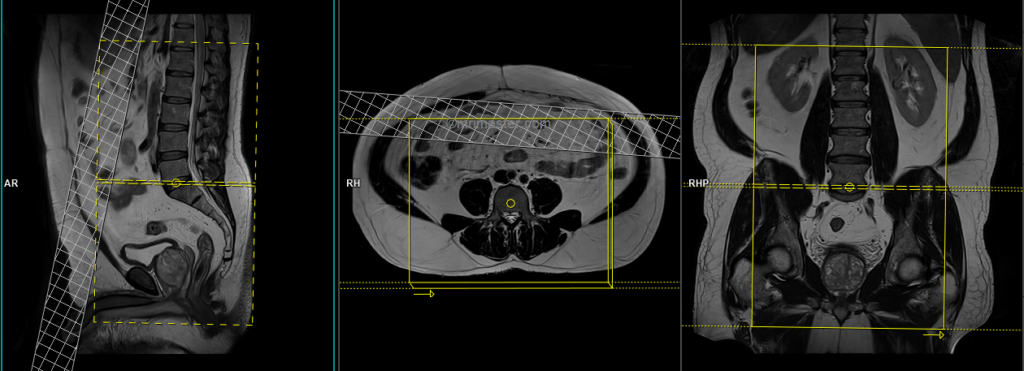

T1 tse coronal 3mm

Plan the coronal slices on the sagittal plane; angle the planning block parallel to the spinal canal. Check the positioning block in the other two planes. An appropriate angle must be given in the axial plane (parallel to the right and left psoas muscle). Check the positioning block in the sagittal plane; FOV must be big enough to cover the whole lumbosacral plexus from L1 down to the pubic symphysis (normally 350mm). Slices must be sufficient to cover the nerves from the anterior border of the symphysis pubis to the median sacral crest. Adding a saturation band in front of the coronal block will reduce artifacts from breathing and peristalsis.

Parameters

TR 400-600 | TE 15-25 | SLICE 3 MM | FLIP 150 | PHASE R>L | MATRIX 512X380 | FOV 350-350 | GAP 10% | NEX(AVRAGE) 2 |